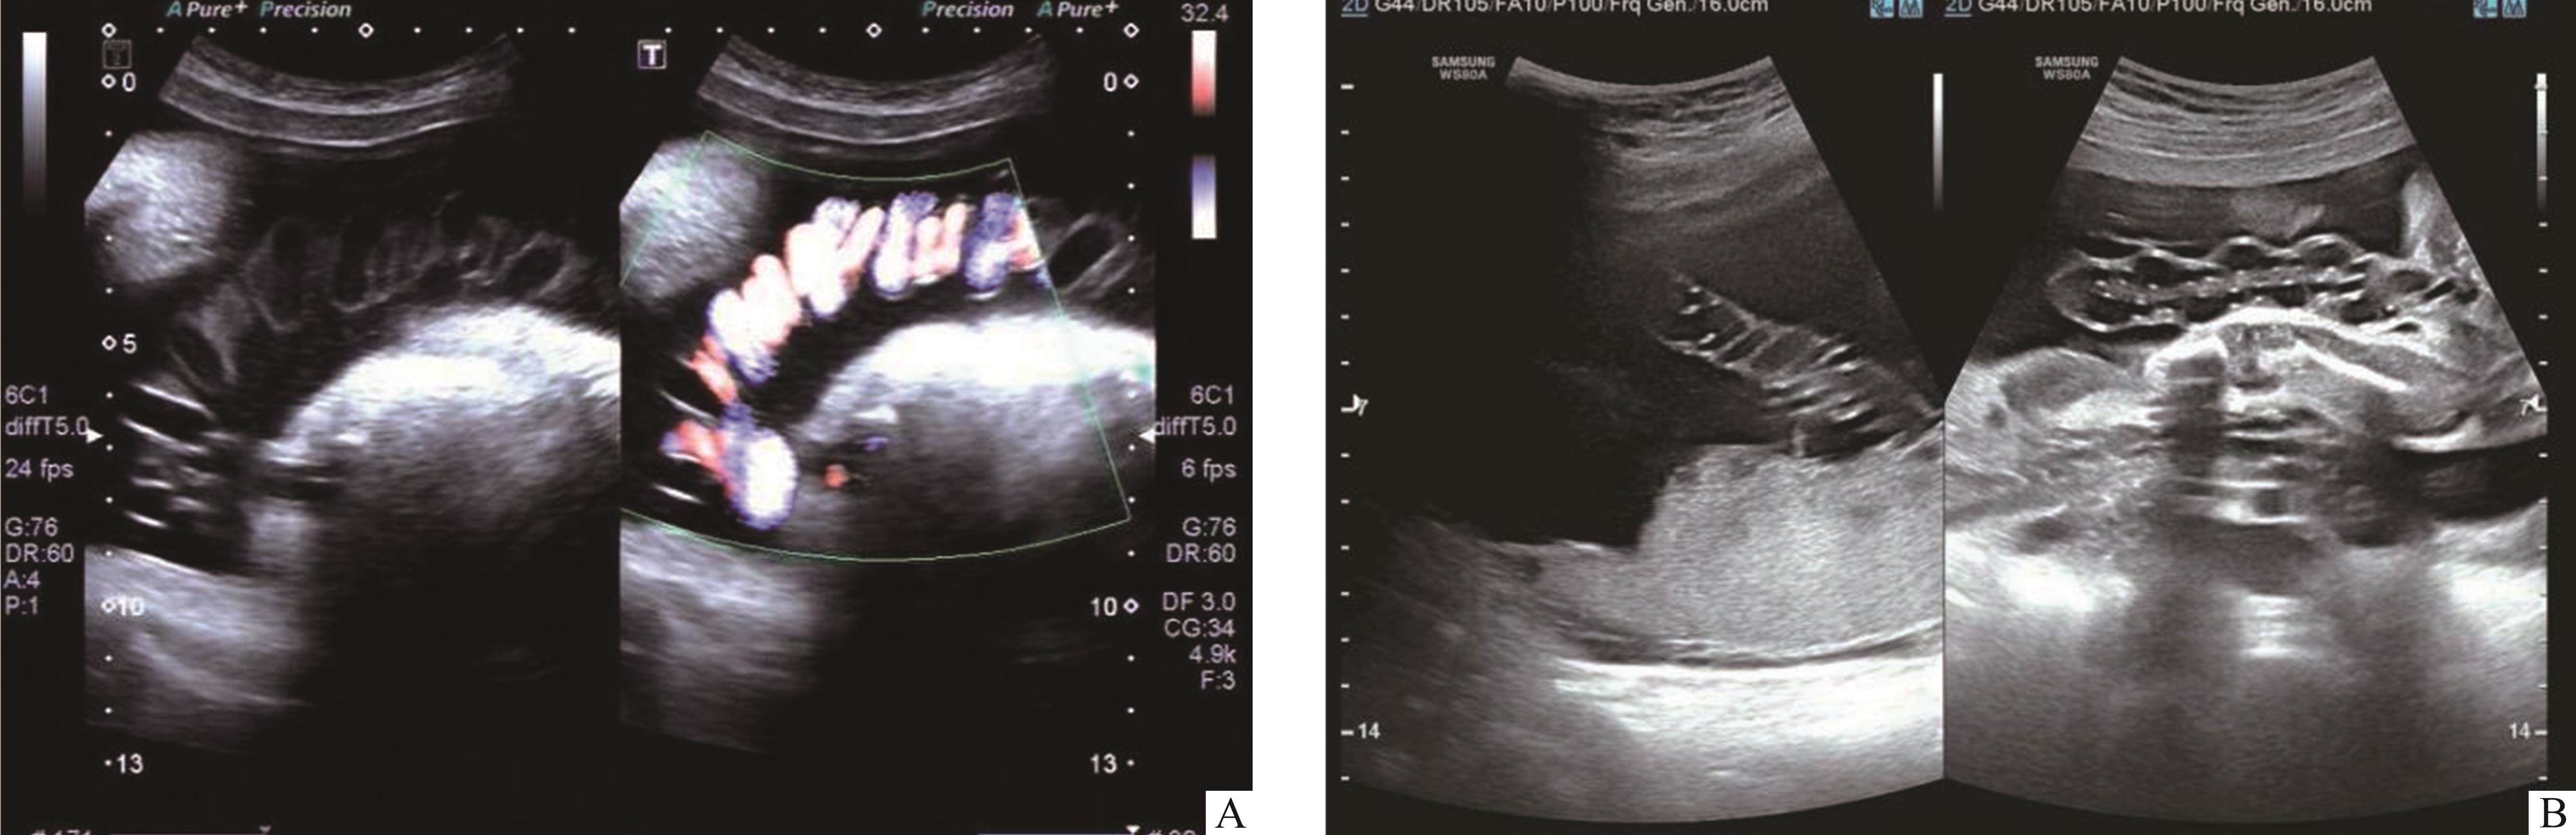

选取2022年11月至2024年11月期间在长沙市妇幼保健院产科门诊就诊、进行规律产检并住院生产、二维超声检查及彩色多普勒超声发现脐带螺旋密集的孕妇作为研究对象(n=262)。纳入标准[1, 6-7]:二维超声检查及彩色多普勒血流成像(color doppler flow imaging,CDFI)发现脐带螺旋圈数≥l2周,脐静脉和脐动脉管径变窄,在不同层次的长轴切面呈密集绳索状、麻花状或对称串珠状等声像(图1),脐带包膜和血管壁的线状强回声与脐带长轴相交角度变小或接近水平位。排除标准:1)双胎妊娠;2)脐带其他异常(如脐带真结、脐带囊肿等);3)胎盘异常(如胎盘早剥、胎盘肿瘤等);3)胎儿畸形;4)严重产科合并症,如子痫前期和溶血、肝酶升高及血小板减少(hemolysis, elevated liver enzymes, and low platelets,HELLP)综合征;5)合并全身性疾病,如自身免疫性疾病(系统性红斑狼疮、抗磷脂综合征等)、未控制的内分泌疾病(甲状腺功能异常、库欣综合征等)。